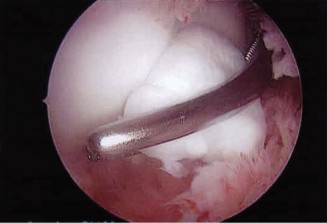

Posterior access is gained via a direct posterior portal (trans-tricipital) and a posterolateral portal. Upon entering the posterior compartment, a localized synovectomy is performed using a mechanical shaver to improve visualization. The posteromedial osteophyte is immediately identified, often accompanied by a "kissing lesion" of chondromalacia on the corresponding olecranon fossa.

Using a 4.0 mm motorized burr, the osteophyte is carefully resected. The resection is meticulously limited to the hypertrophic bone. The surgeon constantly references the native medial cortex of the olecranon, ensuring it is not violated. We dynamically extend the elbow under direct visualization to confirm that the mechanical impingement has been completely eradicated and that full, impingement-free terminal extension is achieved. The joint is thoroughly irrigated to remove all bone debris, and the portals are closed with simple non-absorbable sutures.